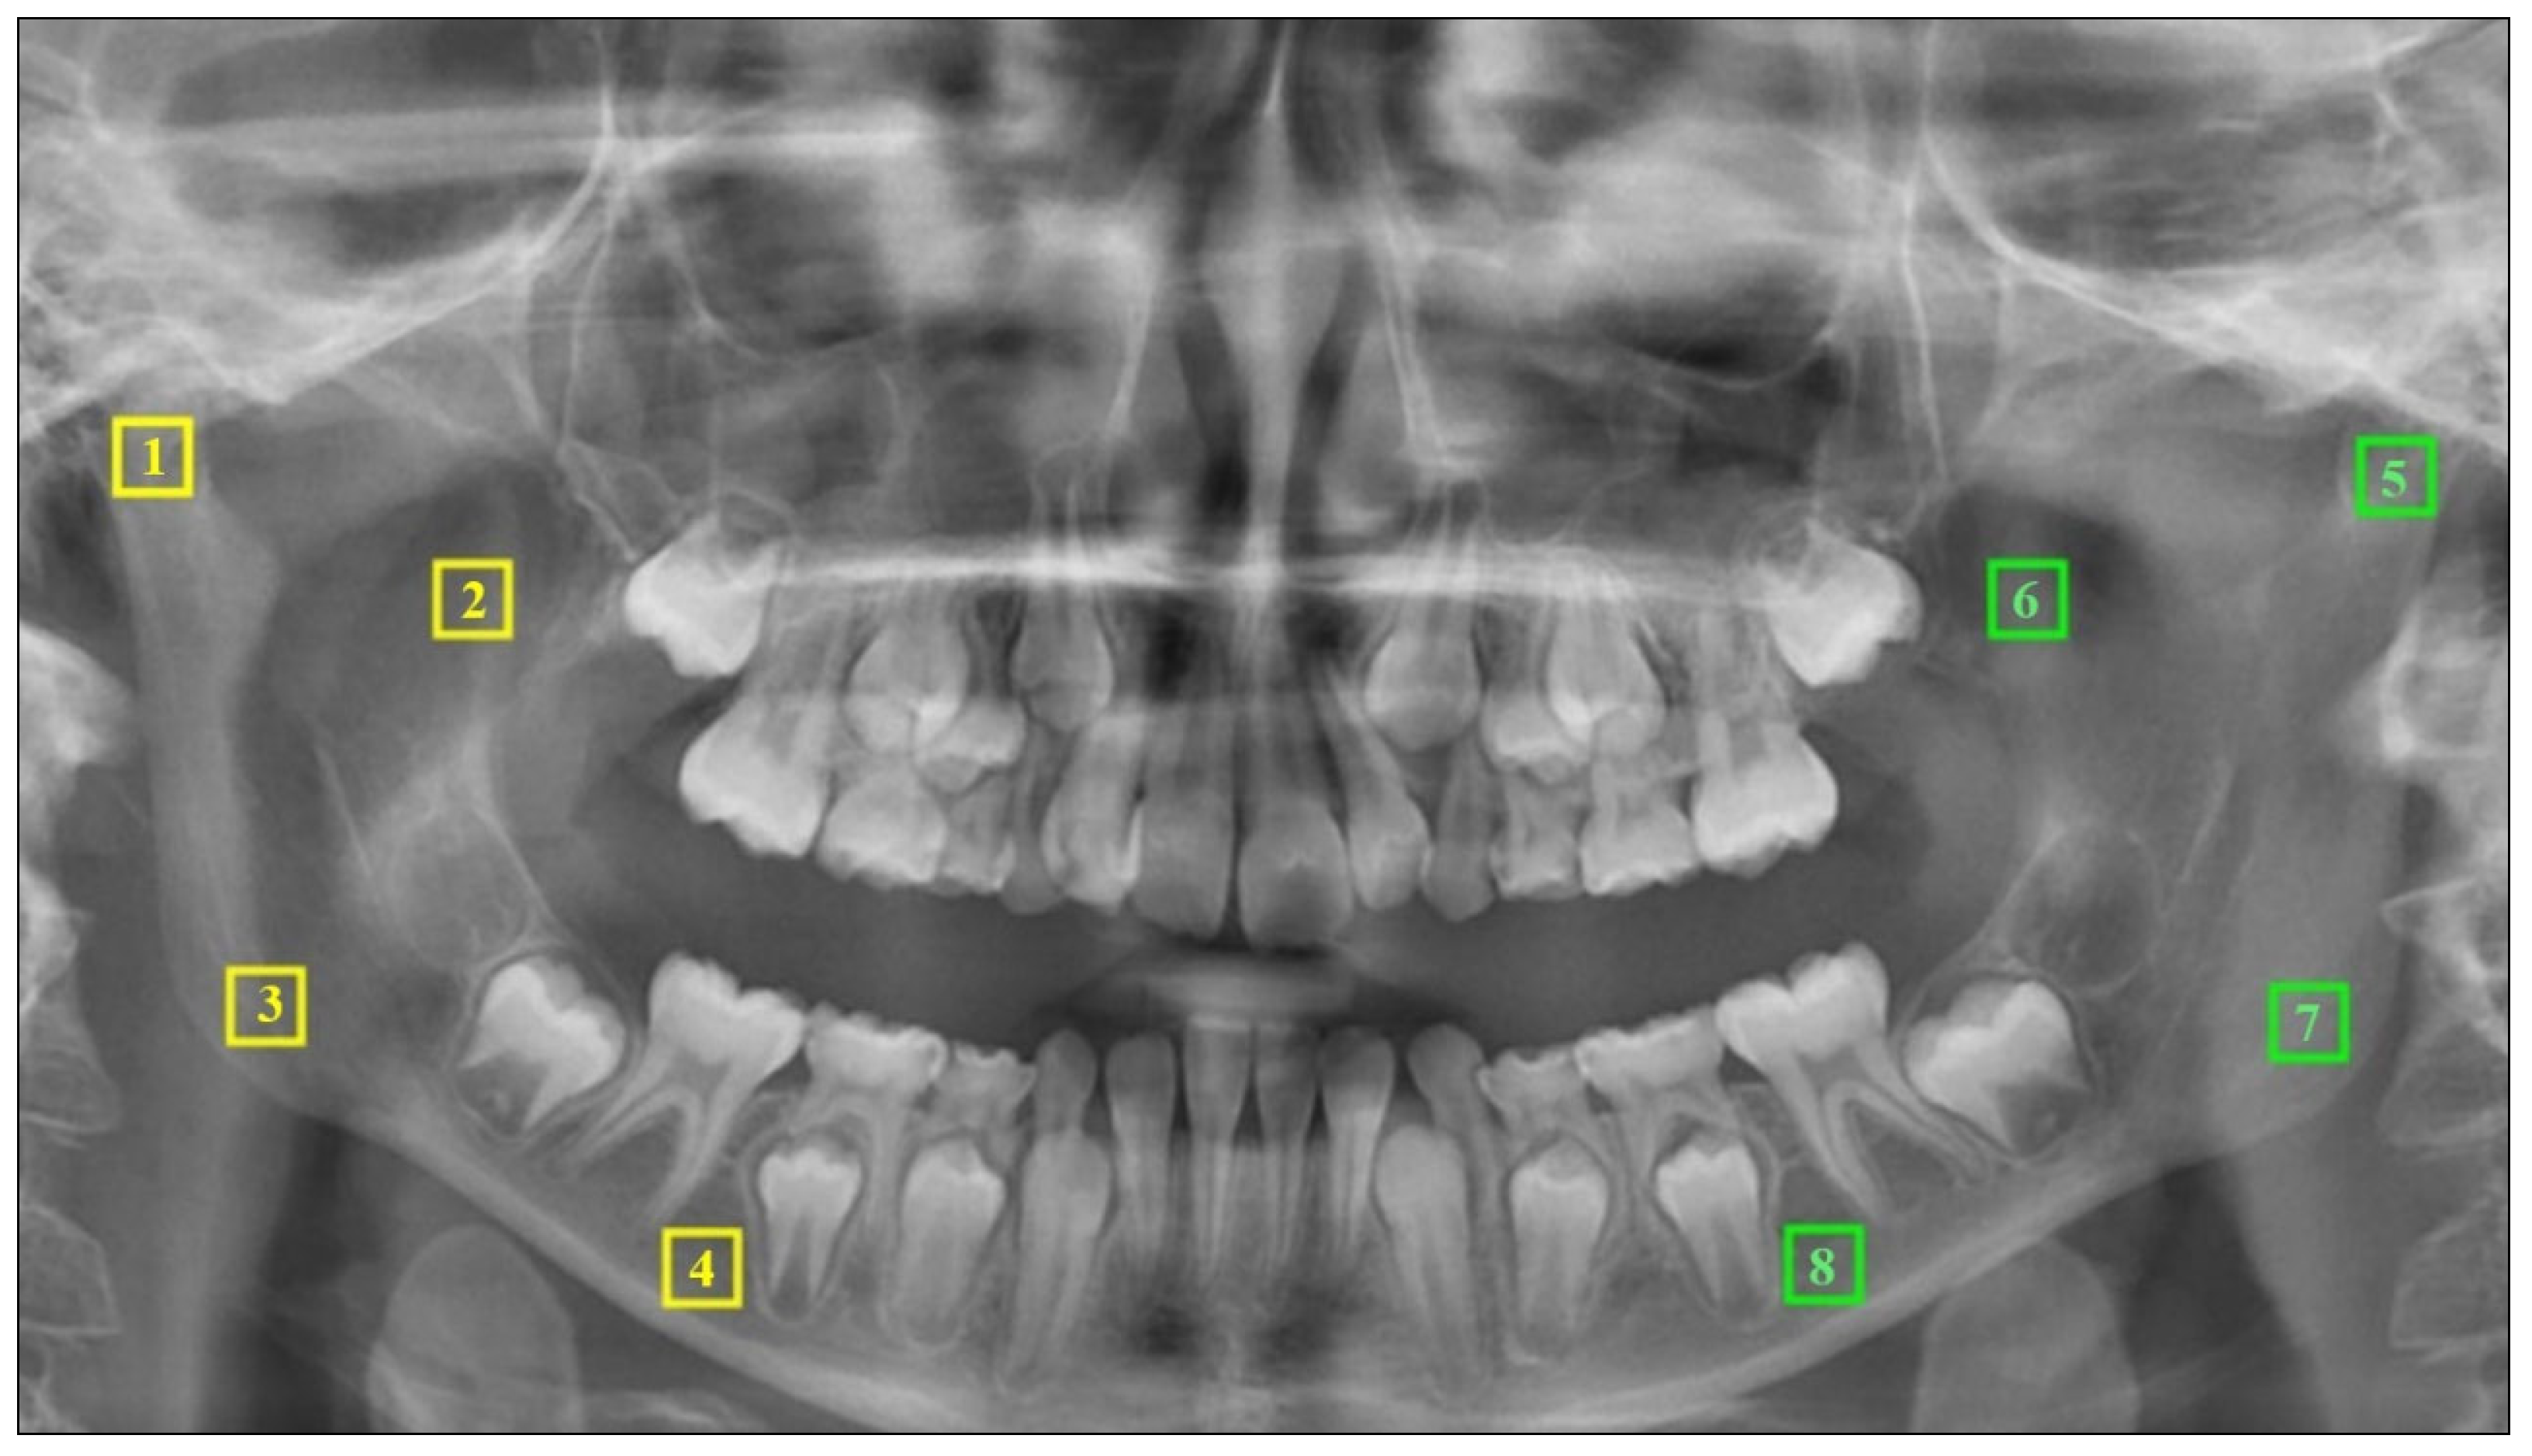

2.4. Fractal Analysis